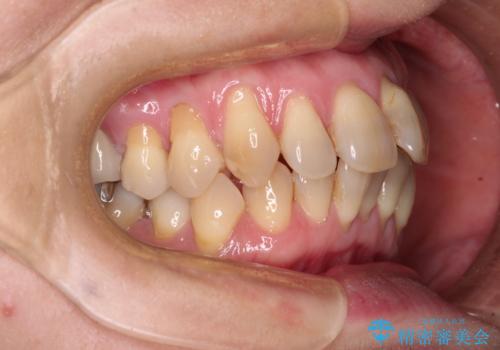

- 上下前歯のデコボコと、奥歯の銀歯を気にして来院された患者様です。

仕事柄あまり目立つ装置は付けることは避けたいとのことで、インビザラインによるマウスピース矯正を行うこととしました。

概ね歯列が整ったところで銀歯の全てをセラミッククラウンなどに置き換え、その後インビザラインを1セット使用して仕上げていくこととしました。

矯正治療の後半にはホワイトニングもされ、スッキリした口元に仕上げることができました。